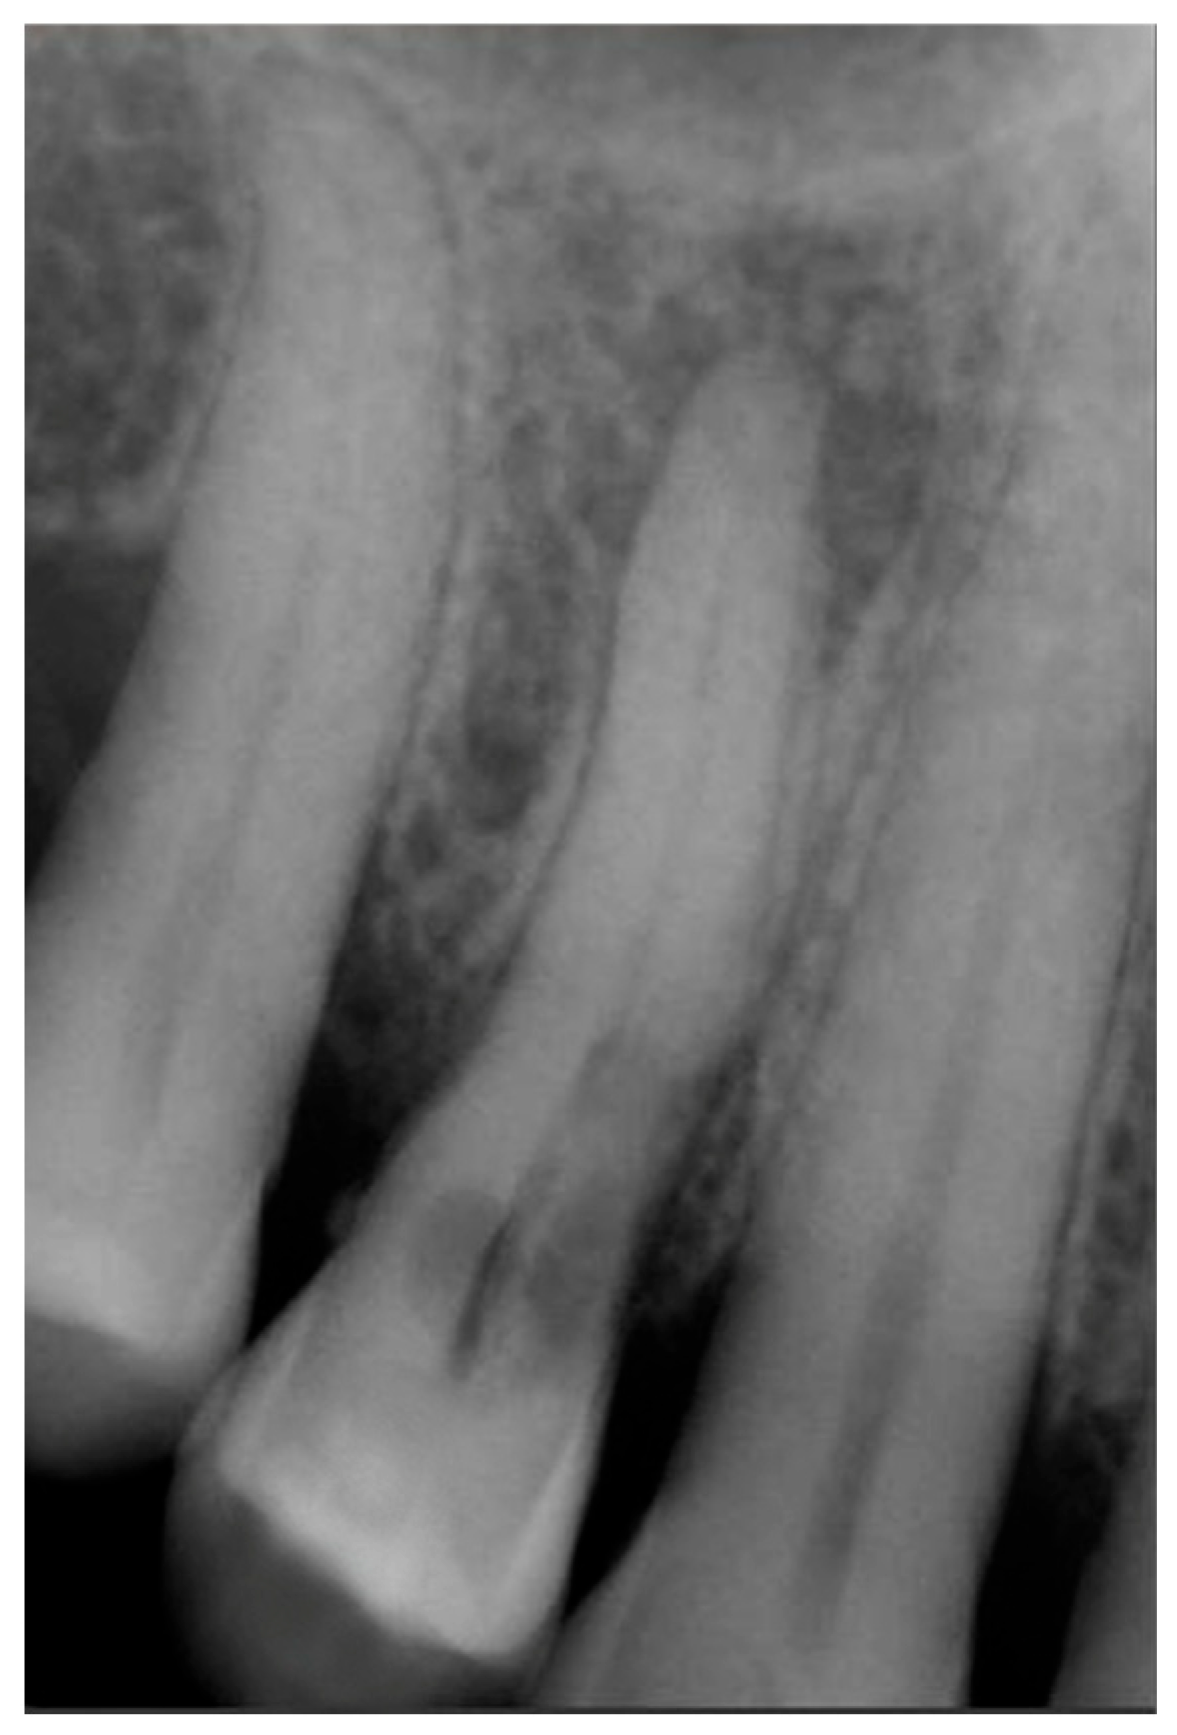

Signs of parafunctional habits and bruxism were noted, along with compromised periodontal status and poor oral hygiene. Multiple carious lesions were present, and the patient exhibited a gag reflex during examination. The patient presented complaining of spontaneous pain and pain upon mastication in the right maxillary region. Tooth 1.4 showed significant pain on percussion and a pathological periodontal probing depth at the mesiolingual site. Intraoral radiography revealed an extensive cervical root resorption zone and a periapical lesion (PL) (Figure 1).

Figure 1.

Intraoral radiography of tooth 1.4 showing root resorption, LP and EPL with mesiocervical widening of the lamina dura space.